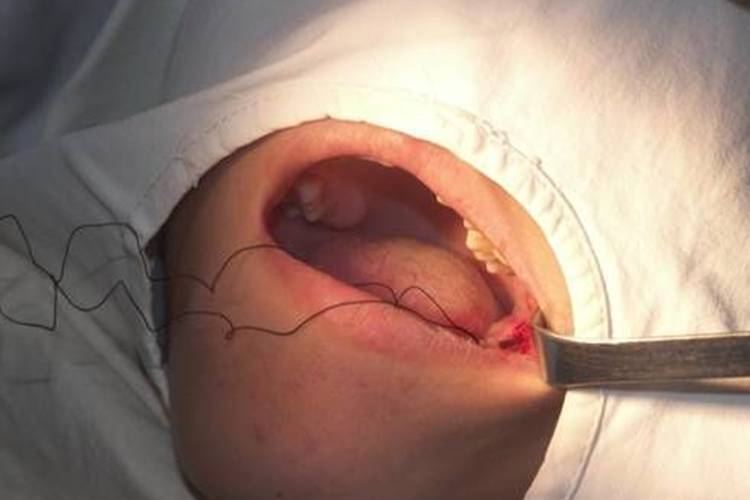

拔牙创口处理及缝合

由于去骨和分牙会产生碎片或碎屑,牙拔除后应认真清理干净牙槽窝,如有炎性肉芽组织,应予以刮除。低位或埋伏阻生牙的牙冠常有牙囊包绕,有的已形成含牙囊肿,也应一并去除。

拔牙后游离的牙龈缘或翻开的黏骨膜瓣应予缝合,使组织复位,以缩小创口,保护血凝块,防止术后出血,有利于创口愈合。